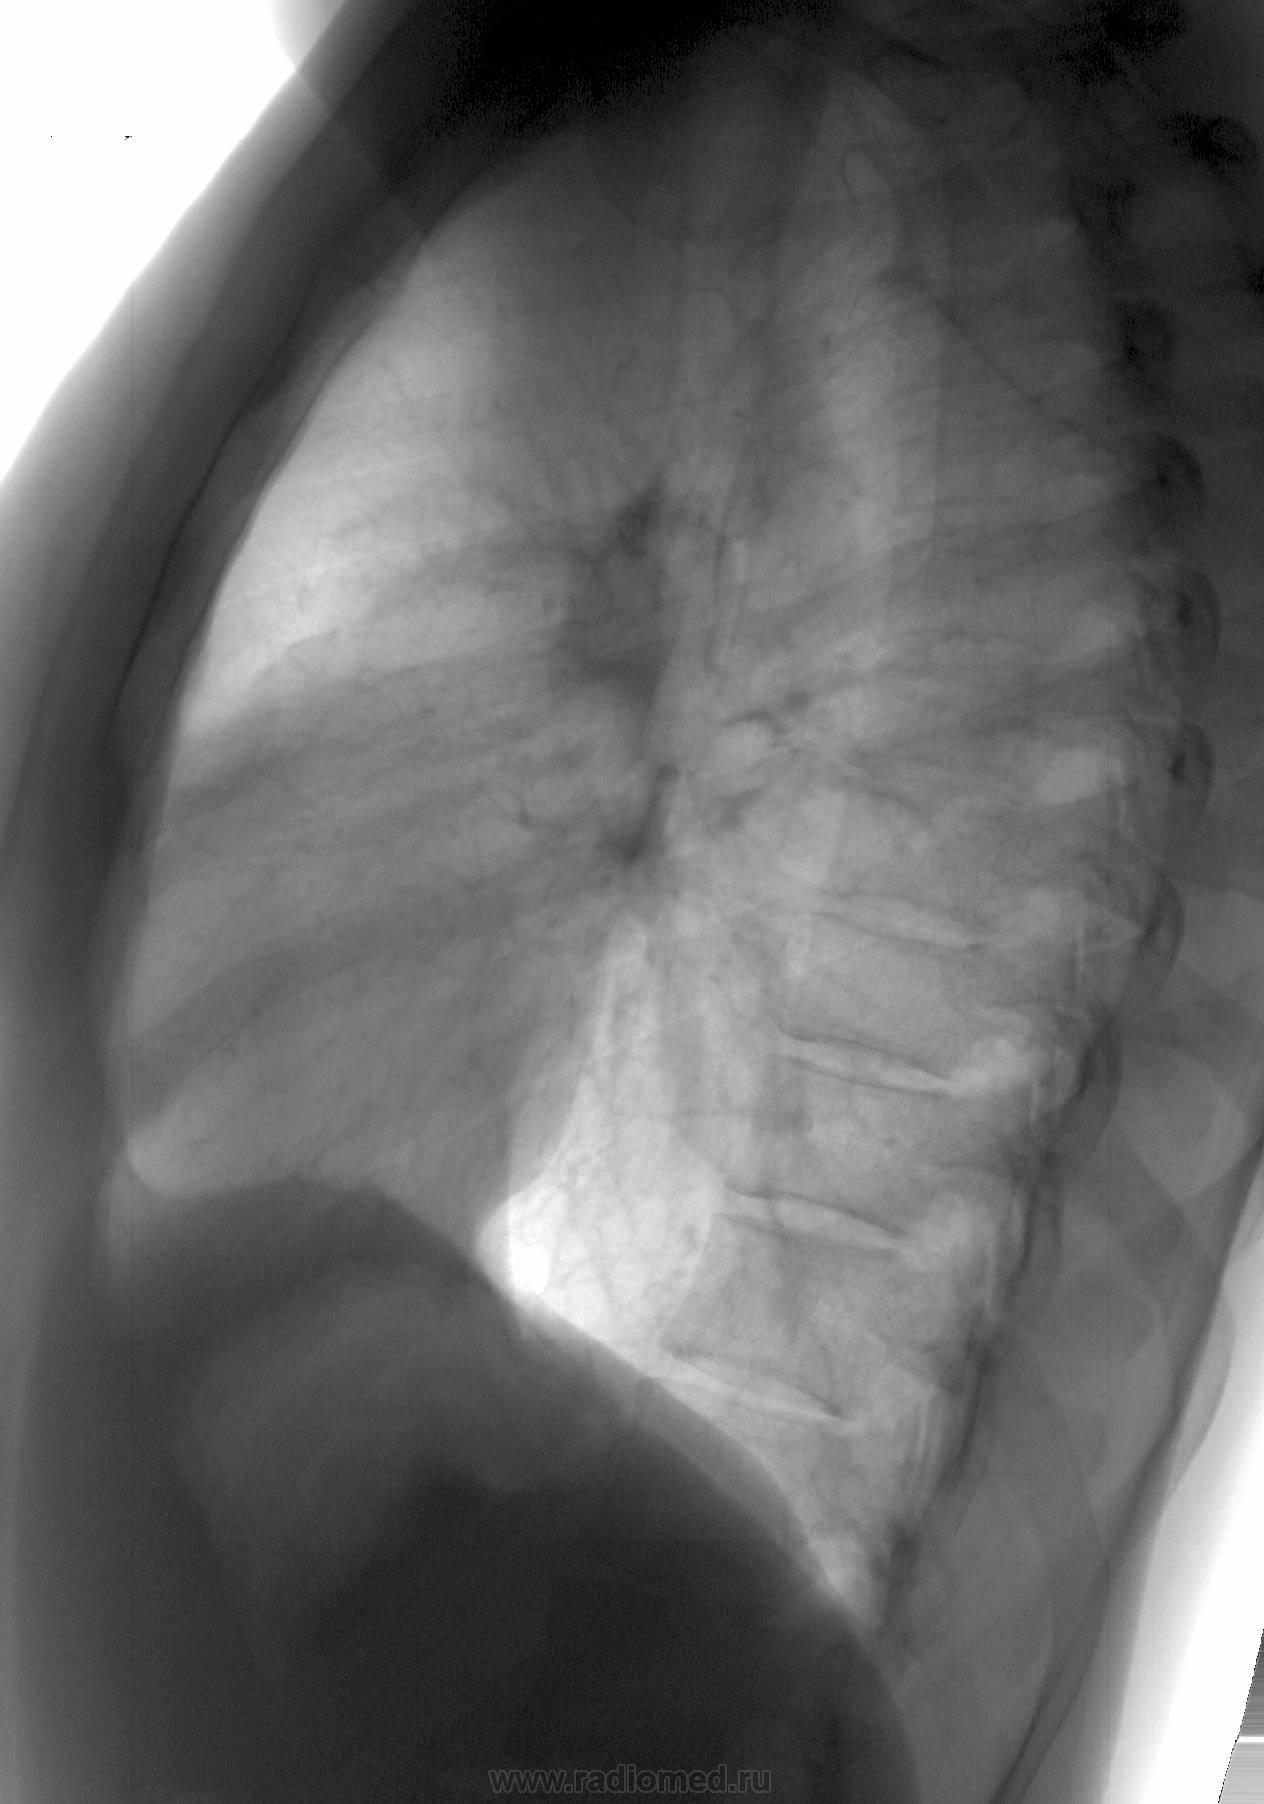

Молодая барышня 28 лет. На момент проведения ц ФГ жалоб нет. Представлена для контроль аналоговая рентгенограмма двухнедельной давности. Динамика отсутствует (посему не выставляю)

В тот же день проведена КТ (о результате информирован лечащим врачом). Ваше мнение?

Шаровидная тень: в S4 в/доли слева (1 случай) и S10 н/доли справа (2 случай)

Татьяна Валентиновна, асолютно согласен. что основной рентгенологический признак - шаровидные тенеобразования, но...достаточно ли они "шаровидны" и достаточно ли однородны....+молодой, в общем то возраст, + отсутствие существенных жалоб. Конечно, смущает тот факт, что это не первые их ФГ (но у меня то они впервыеwink). Опять же - в С10 (скрывается за тенью печени), в С4 слева (не факт, что раньше было перекрыто левым краем сердца) и, как следствие - не были обнаружены.

Внутрилегочная секвестрация или артериовенозная мальформация.

..... артериовенозная мальформация.

Она самая))). Да, оба случая подтверждены на КТ.